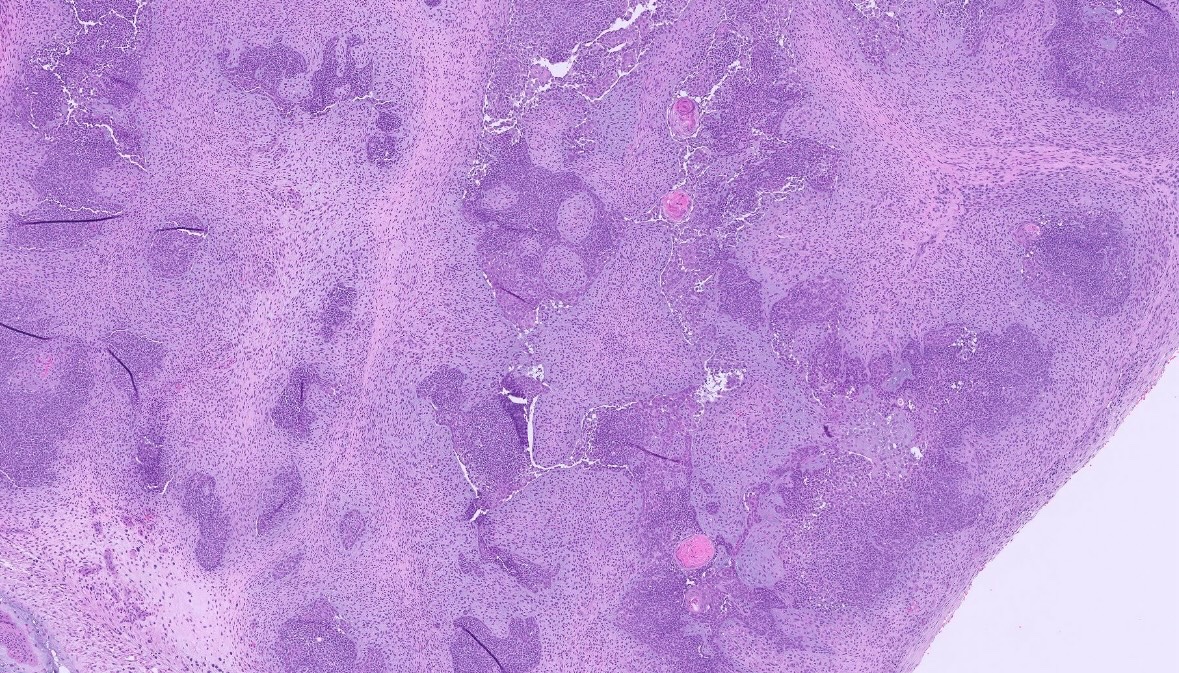

Malignant transformation within an adamantinomatous craniopharyngioma. #pathx #PathTwitter #neuropath #neuropathology #cnspathology